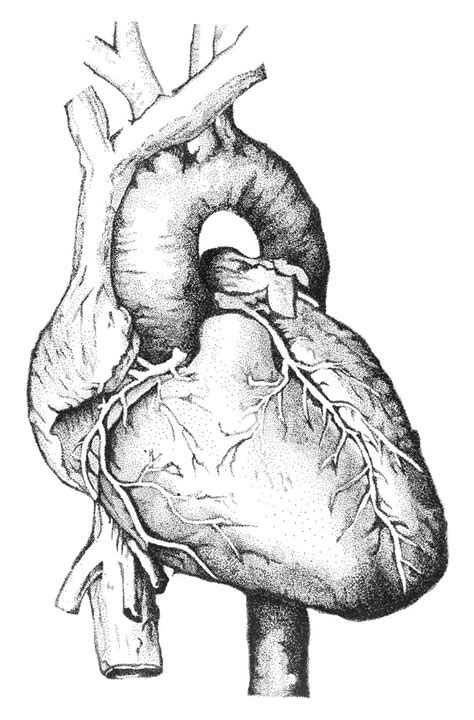

Medical illustration has played a pivotal role in healthcare for centuries, bridging the gap between science and visual communication to enhance patient understanding, guide medical research, and facilitate surgical interventions. The field is graced by a pantheon of master illustrators whose works have not only influenced the landscape of healthcare but also elevated the status of medical art as an invaluable tool for patient education and clinical practice.

Andreas Vesalius (1514-1564) is considered the founder of modern human anatomy. His groundbreaking work, “De Humani Corporis Fabrica” (On the Fabric of the Human Body), published in 1543, revolutionized the understanding of human anatomy and laid the foundation for accurate medical illustrations. Vesalius’s anatomical drawings were remarkably detailed and scientifically precise, challenging centuries-old misconceptions and paving the way for a more thorough understanding of the human body.

While not a medical illustrator per se, Leonardo da Vinci’s (1452-1519) insatiable curiosity and artistic genius extended to the field of anatomy. His anatomical sketches, based on meticulous dissections, revealed a profound understanding of the human body and its mechanics. Da Vinci’s legacy extends beyond the realm of art, influencing medical education and the development of anatomical illustration techniques.